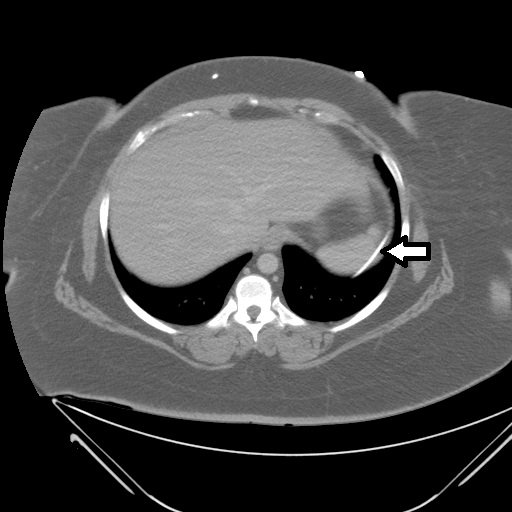

An immediate post-op abdominal x-ray performed after the patient’s VP shunt revision 30 days prior to this ED visit reveals the VP shunt tip in the mid abdomen. A CT of the abdomen performed on the day of the ED visit reveals the VP shunt tip interposed between the spleen and the diaphragm.